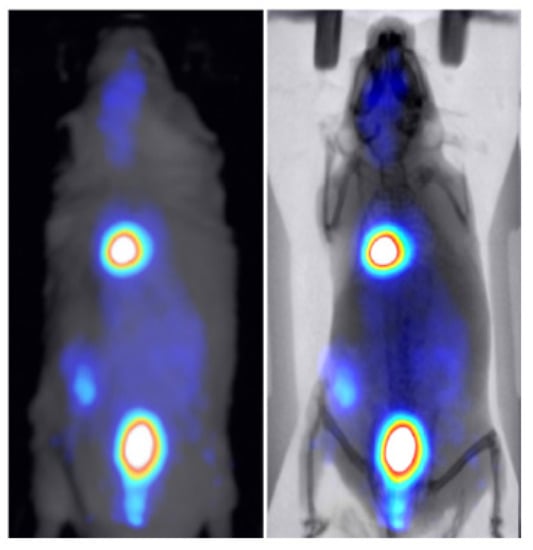

3.2. Animal Mapping during In Vivo Molecular Imaging Experiments